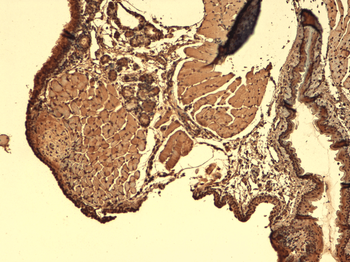

IHC-P staining of human thyroid tumour tissue using NIS antibody (2.5 ug/ml)

IHC-P image of human thyroid cancer tissue using NIS antibody (2.5 ug/ml)

Immunohistochemical staining of paraffin embedded mouse brain tissue using anti-NIS (2.5 ug/ml)